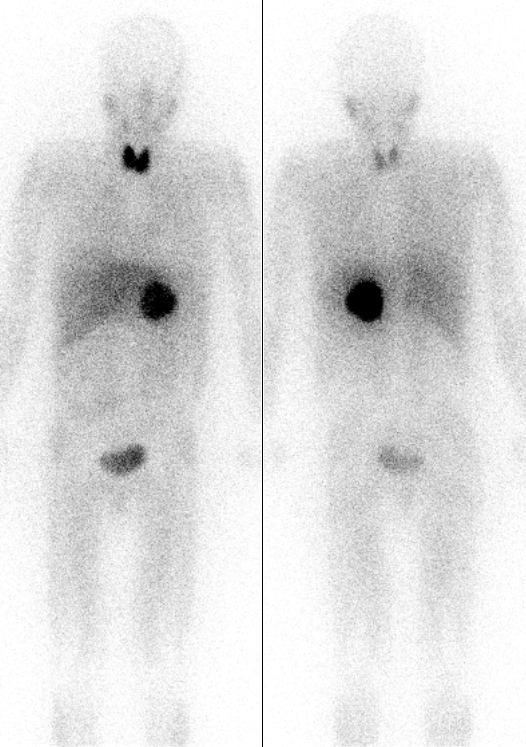

Due to preferential uptake of iodine by the thyroid, radioiodine is extensively used in imaging of and, in the case of I-131, destroying dysfunctional thyroid tissues. Other types of tissue selectively take up certain iodine-131-containing tissue-targeting and killing radiopharmaceutical agents (such as MIBG). Iodine-125 is the only other iodine radioisotope used in radiation therapy, but only as an implanted capsule in brachytherapy, where the isotope never has a chance to be released for chemical interaction with the body's tissues.

Iodine-131 (I131) is a beta-emitting isotope with a half-life of eight days, and comparatively energetic (190 keV average and 606 keV maximum energy) beta radiation, which penetrates 0.6 to 2.0 mm from the site of uptake. This beta radiation can be used for the destruction of thyroid nodules or hyperfunctioning thyroid tissue and for elimination of remaining thyroid tissue after surgery for the treatment of Graves' disease. The purpose of this therapy, which was first explored by Dr. Saul Hertz in 1941, is to destroy thyroid tissue that could not be removed surgically. In this procedure, I131 is administered either intravenously or orally following a diagnostic scan. This procedure may also be used, with higher doses of radio-iodine, to treat patients with thyroid cancer.

The I131 is taken up into thyroid tissue and concentrated there. The beta particles emitted by the radioisotope destroys the associated thyroid tissue with little damage to surrounding tissues (more than 2.0 mm from the tissues absorbing the iodine). Due to similar destruction, I131 is the iodine radioisotope used in other water-soluble iodine-labeled radiopharmaceuticals (such as MIBG) used therapeutically to destroy tissues.

Most medical imaging with iodine is done with a standard gamma camera. However, the gamma rays from iodine-123 and iodine-131 can also be seen by single photon emission computed tomography (SPECT) imaging.

Iodine-124 as the iodide salt can be used to directly image the thyroid using positron emission tomography (PET). Iodine-124 can also be used as a PET radiotracer with a usefully longer half-life compared with fluorine-18 In this use, the nuclide is chemically bonded to a pharmaceutical to form a positron-emitting radiopharmaceutical, and injected into the body, where again it is imaged by PET scan.